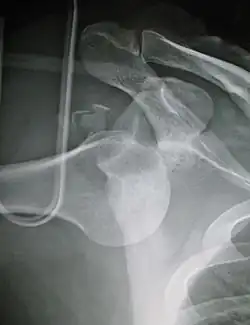

Anterior dislocation of the left shoulder.

A shoulder dislocation often occurs as a result of a fall onto an outstretched arm or onto the shoulder.[3] Diagnosis is typically based on symptoms and confirmed by X-rays.[2] They are classified as anterior, posterior, inferior, and superior with most being anterior.[2][1]